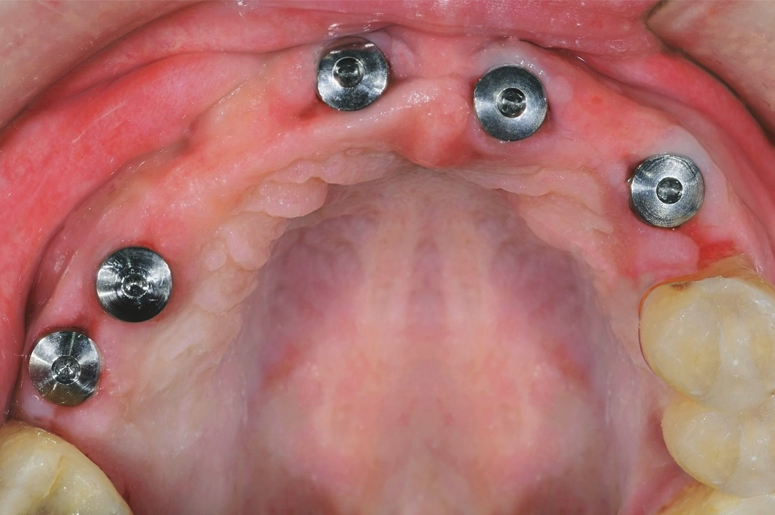

Difficult Cases

We treat patients when other providers cannot manage.